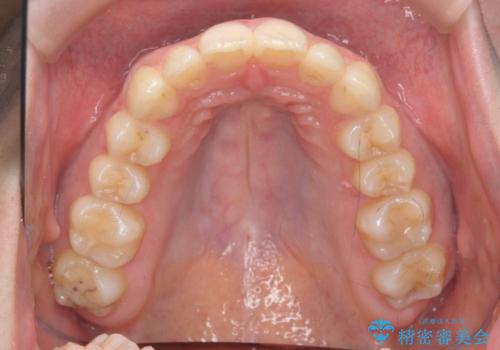

- 上の前歯が出ている感じを治したい、と矯正治療を希望され来院されました。

上顎歯列の突出感を改善すべくIPRを行い、下顎歯列を小さくすることで前歯の角度を大きく是正します、。

下顎歯列は元々前歯が1本少なく小さなアーチでしたが、下顎に合わせ上顎歯列もIPRを行い小さくすることで出っ歯感を大きく改善することが出来ました。